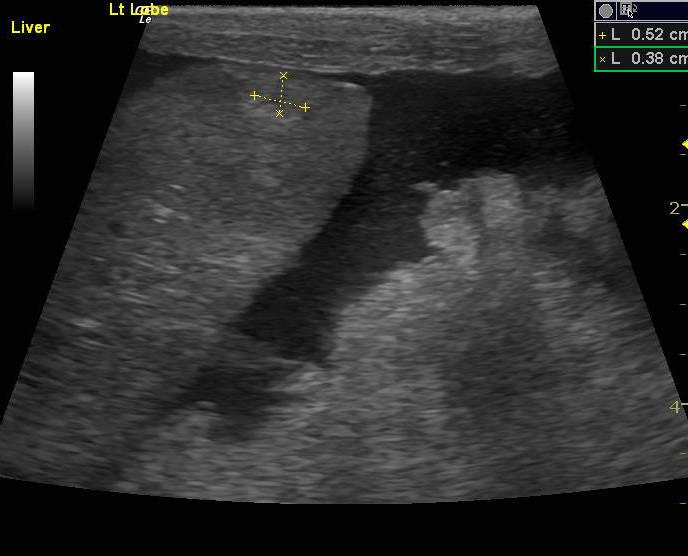

The abdomen in this patient presented moderate amount of echogenic free fluid. Multiple heterogenous nodular changes were noted which were hypoechoic and hyperechoic throughout the liver. This is suggestive for metastatic event. Some internal structure deviation was noted. The deep right liver revealed a collapsed gallbladder with surrounding parenchymal nodular changes with impingement upon the gallbladder. The vena cava was normal. The hepatic veins were subnormal in size. This is indicative of an increased possibility of feline infectious peritonitis. The pancreatic region revealed multiple nodular hypoechoic changes with irregular surrounding omentum.

Pancreas: carcinoma. Liver: carcinoma (suspected metastatic).

FNA of liver revealed carcinoma (suspected metastatic). FNA of pancreas: carcinoma. Comments: Given the appearance of the slides as well as the sonographic description, the pancreas is likely the site of primary neoplasia, with metastases to the liver. The neoplastic cells appear epithelial but do not contain zymogen granules typical of normal pancreatic cells. This could be because the cells are sufficiently anaplastic as to have lost this feature, but other sources should be considered as well.